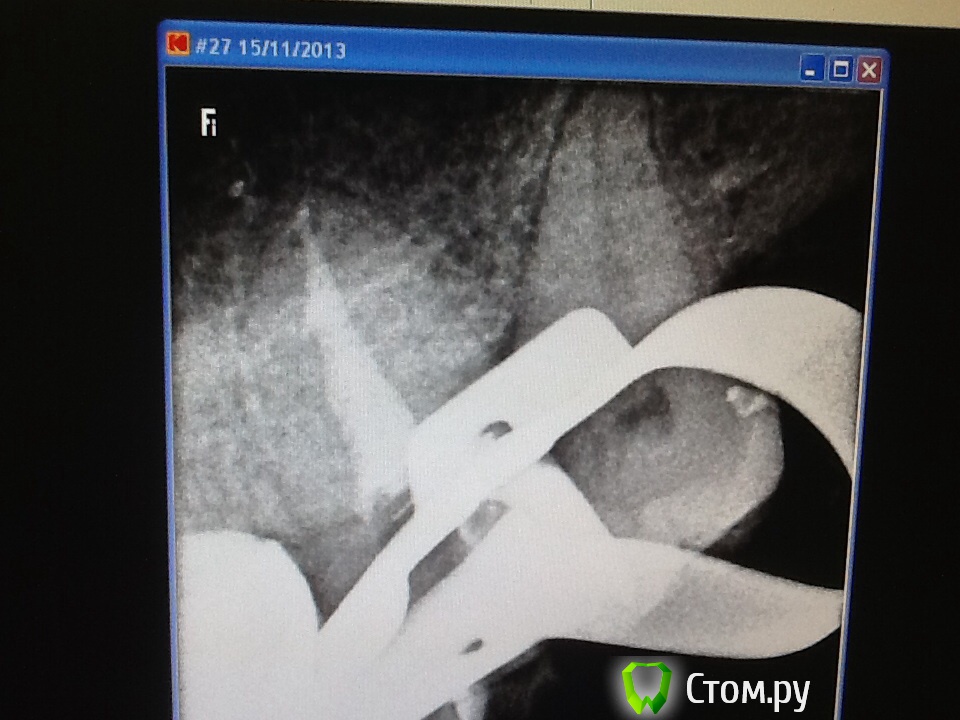

Л Ю С Я Опубликовано 25 ноября, 2013 Автор Поделиться Опубликовано 25 ноября, 2013 Спасибо всем за советы по поводу паковки сквирт. На фантомах попробовать не получилось- вон куча зубиков вторую неделю киснет в формалине - ну просто некогда, все пробую во рту. Действительно, плюется намного меньше.А вот этот зуп меня не порадовал. Как я не пыталась в бинокулярах разглядеть вход в третий канал, ничего не получилось- было много хлорки, эдта, спирт, не знаю вроде гутта затеклаА может силер? 6 Ссылка на комментарий

ger_berra Опубликовано 25 ноября, 2013 Поделиться Опубликовано 25 ноября, 2013 (изменено) Спасибо всем за советы по поводу паковки сквирт. На фантомах попробовать не получилось- вон куча зубиков вторую неделю киснет в формалине - ну просто некогда, все пробую во рту. Действительно, плюется намного меньше.image.jpgimage.jpgА вот этот зуп меня не порадовал. Как я не пыталась в бинокулярах разглядеть вход в третий канал, ничего не получилось- было много хлорки, эдта, спирт, не знаю вроде гутта затеклаimage.jpgА может силер?Люсь,последний снимок -бомба! Очень нравится!Помыли отменно.И,кмк,не важно,гутта там или силер. Изменено 25 ноября, 2013 пользователем ger_berra Ссылка на комментарий